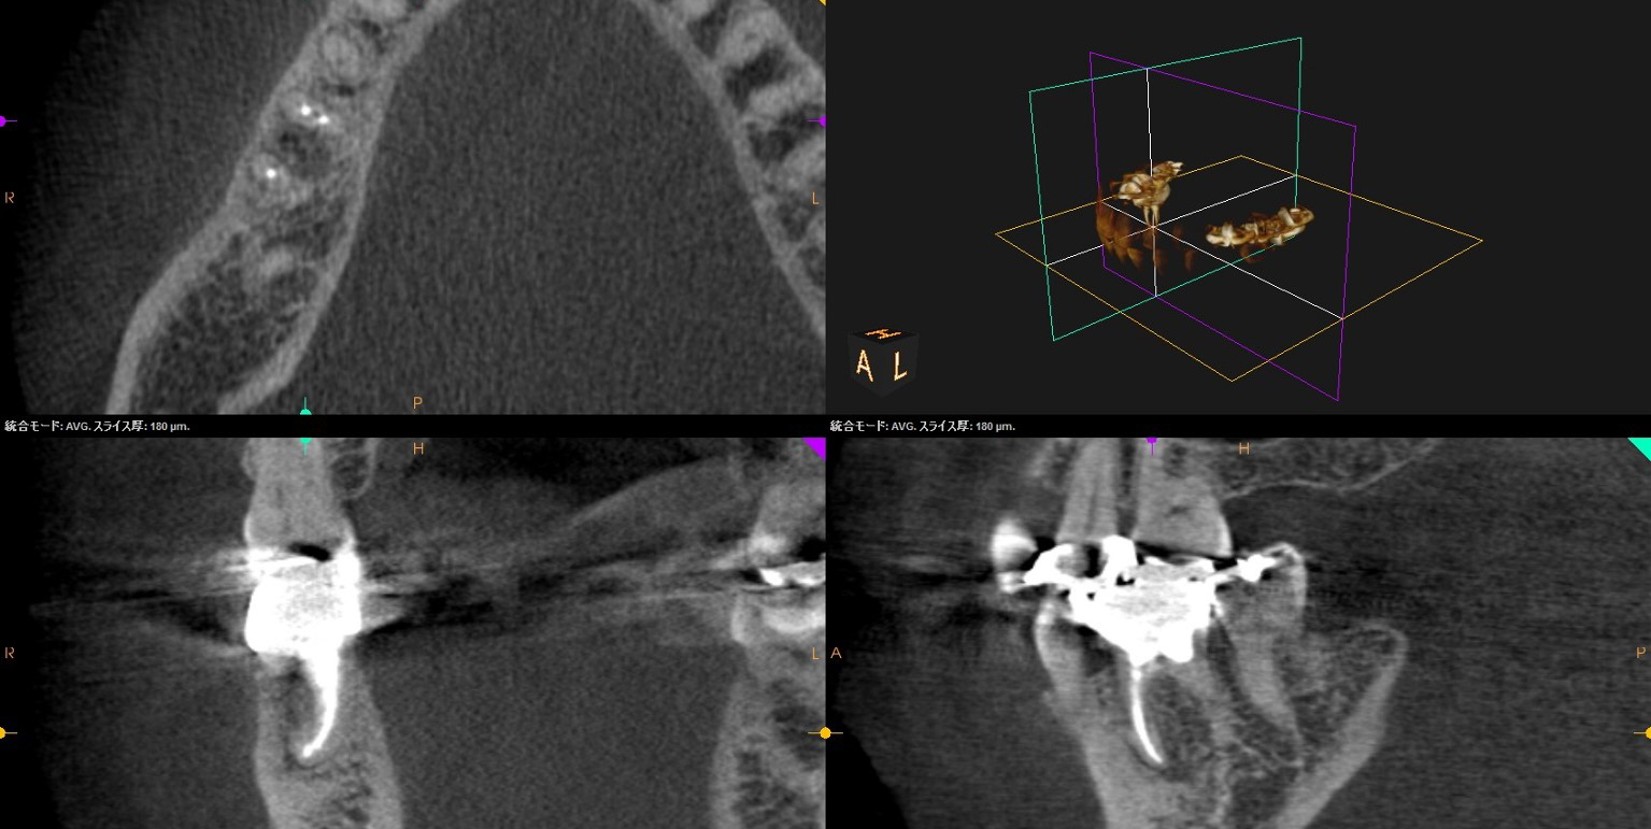

• 初診来院時 根尖性歯周炎により骨吸収あり

• 自費の感染根幹治療終了直後

• 自費感染根幹治療6か月後、骨の回復がみられた

• CT撮影による三次元診断で、見落としのない精密治療